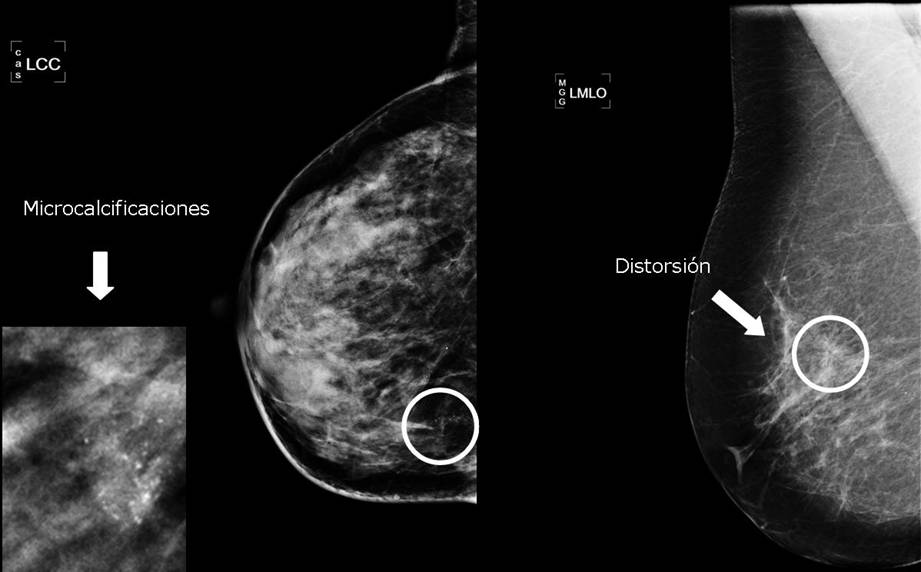

Com a mètode diagnòstic en casos seleccionats en els que el radiòleg prevegi que es pot extreure tota la lesió amb marges lliures i que tingui poques probabilitats de ser maligne:

- Petites distorsions de l’arquitectura.

- Cúmuls de microcalcificacions poc sospitoses o com a mètode terapèutic, està en fase d’avaluació.